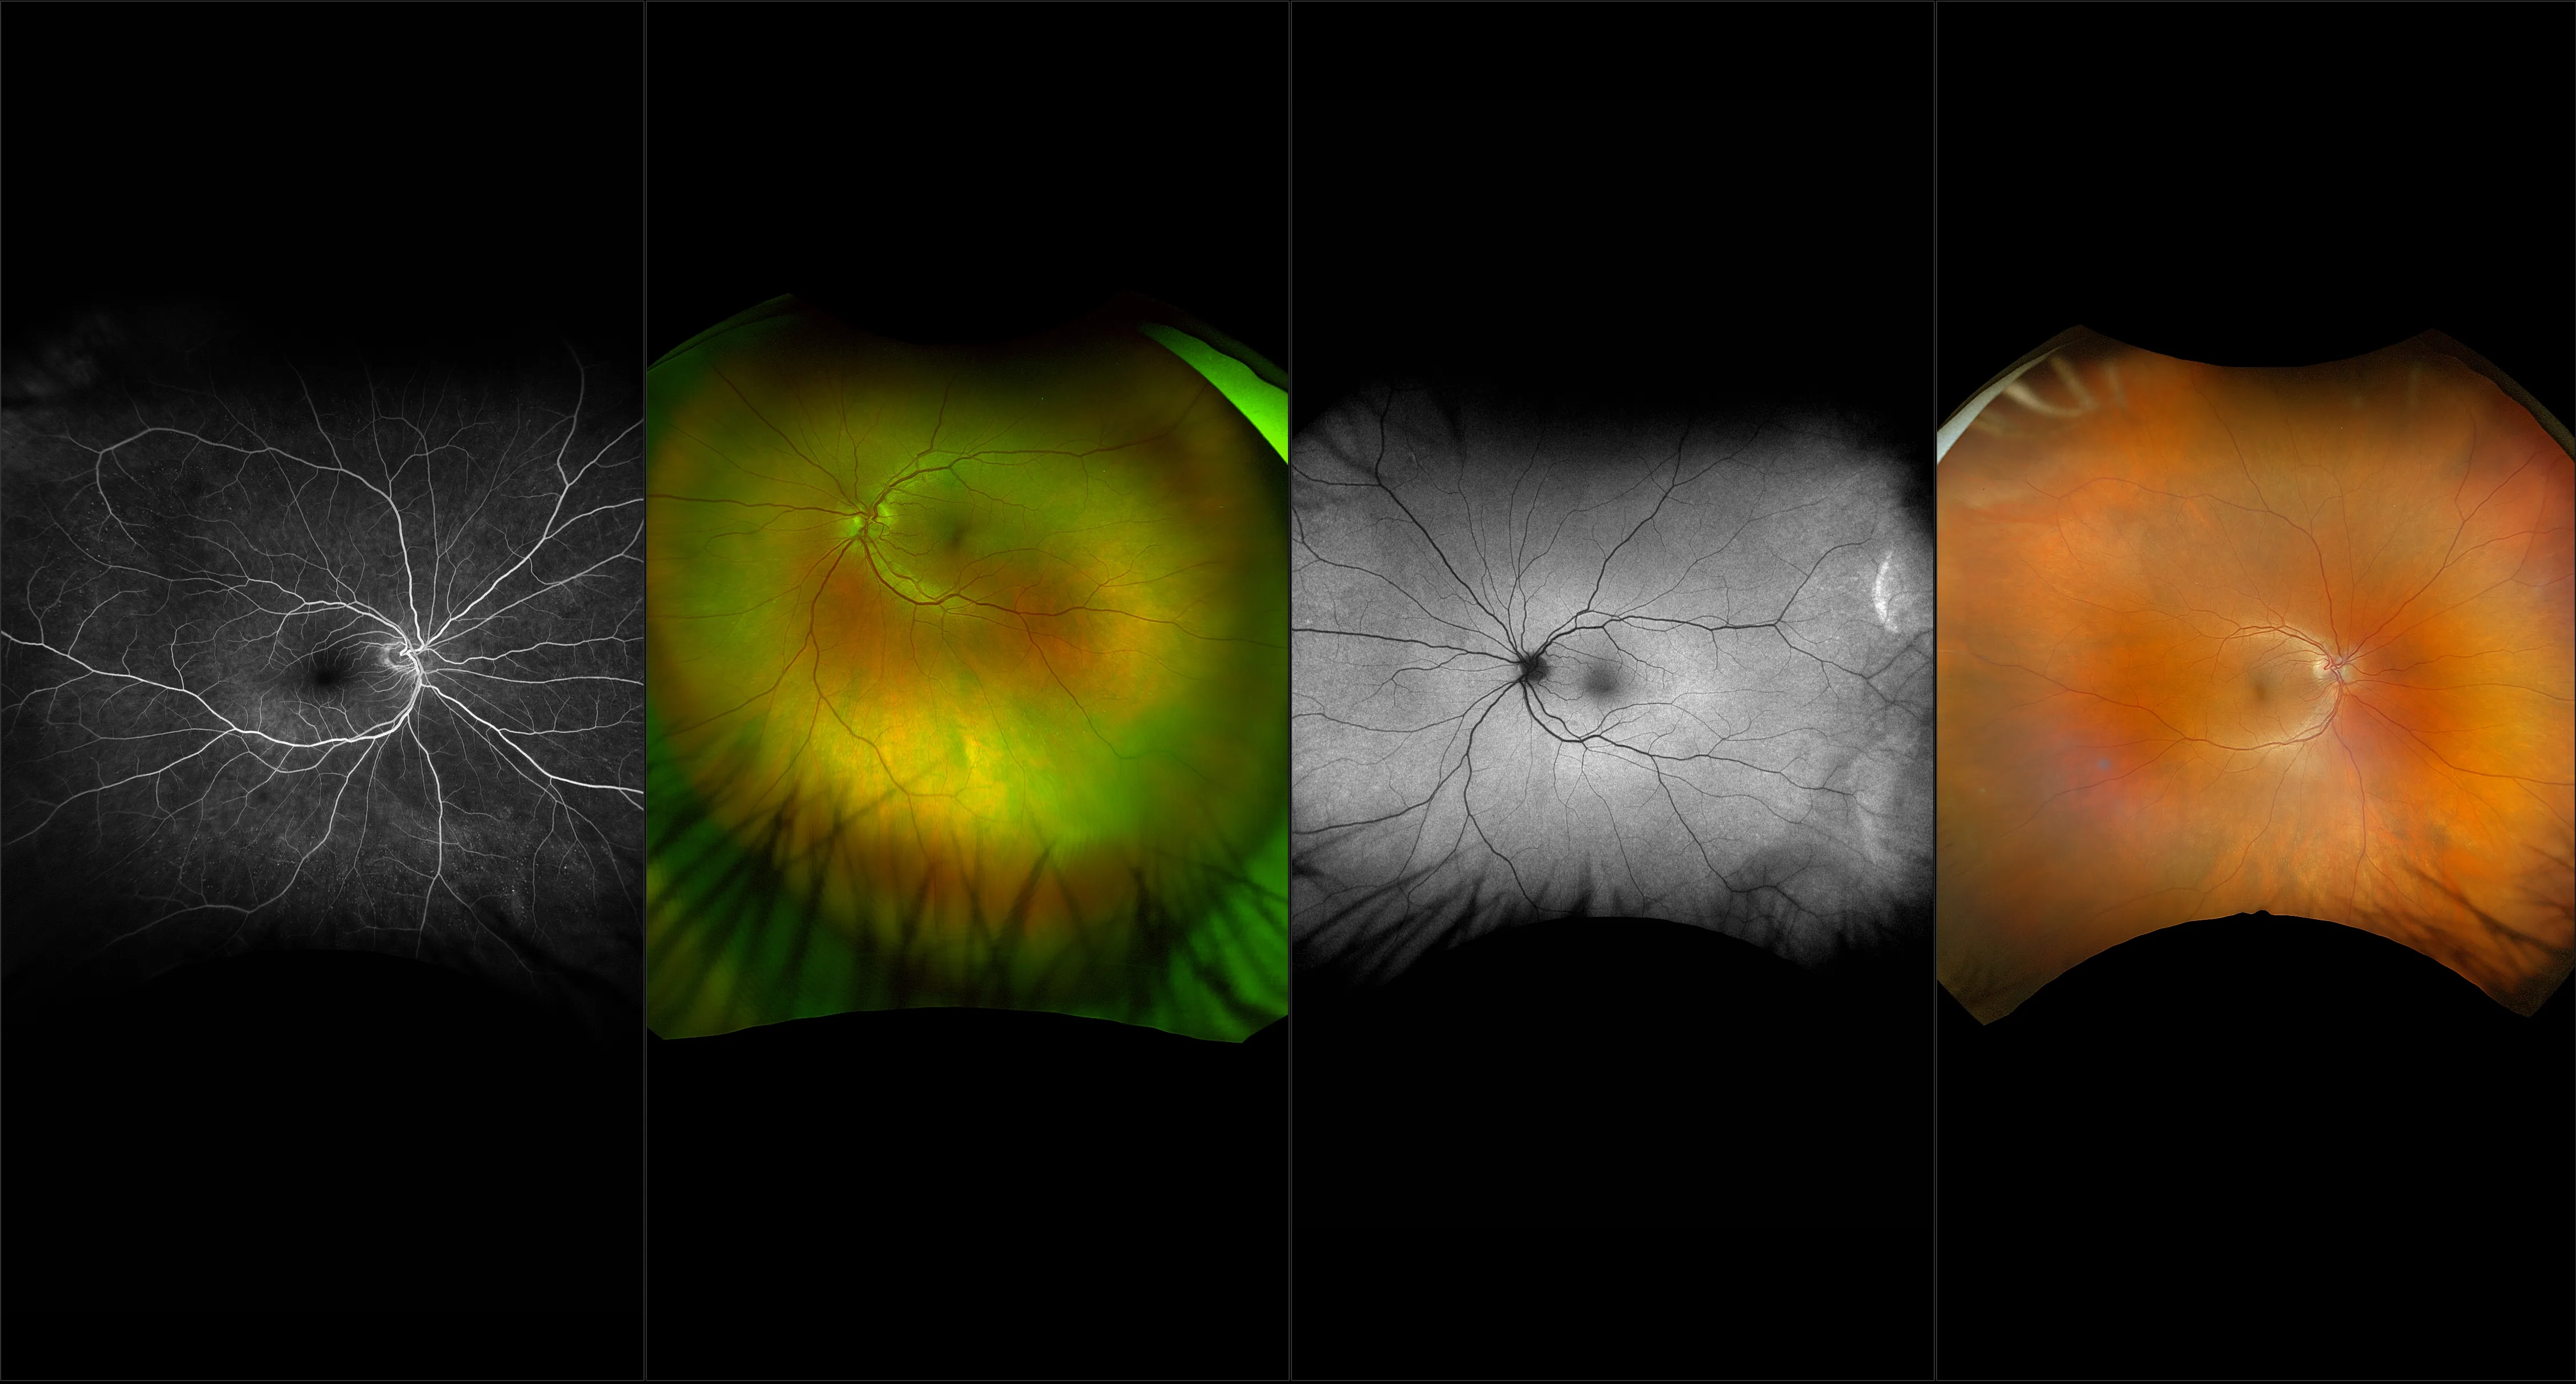

optomap® Recognizing Pathology

This material is designed as a searchable reference resource to support clinical decision-making. The information contained here should be used as general guidance when viewing optomap and OCT images from Optos devices. The differential diagnosis should be made under the direction of the responsible physician. These images were taken on the latest ultra-widefield optomap devices.

The Cases and Images

optomap Recognizing Pathology is searchable by pathology and/or optomap image modality. You may search by multiples of each selection. Each individual case is represented by the accompanying thumbnail image. Most cases include several different optomap image modalities. To view a full description of the case, please click on the thumbnail. Each image in the case will be made available through our OptosAdvance software which provides multi-dimensional visualization of digital images to aid in the analysis of anatomy and pathology. Support and pathology definitions can be found by selecting one of the buttons, above. Should you have questions, please complete the form below.